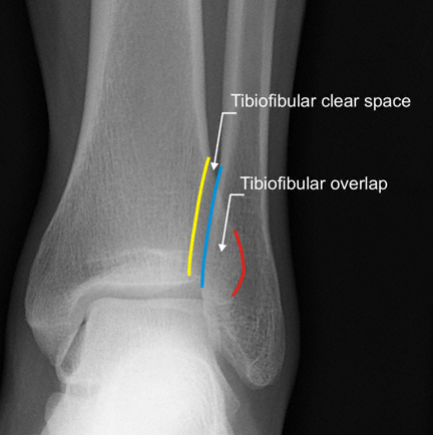

Ankle fracture Facts One of the most common skeletal injuries seen by physicians Fractures of the malleoli ar…